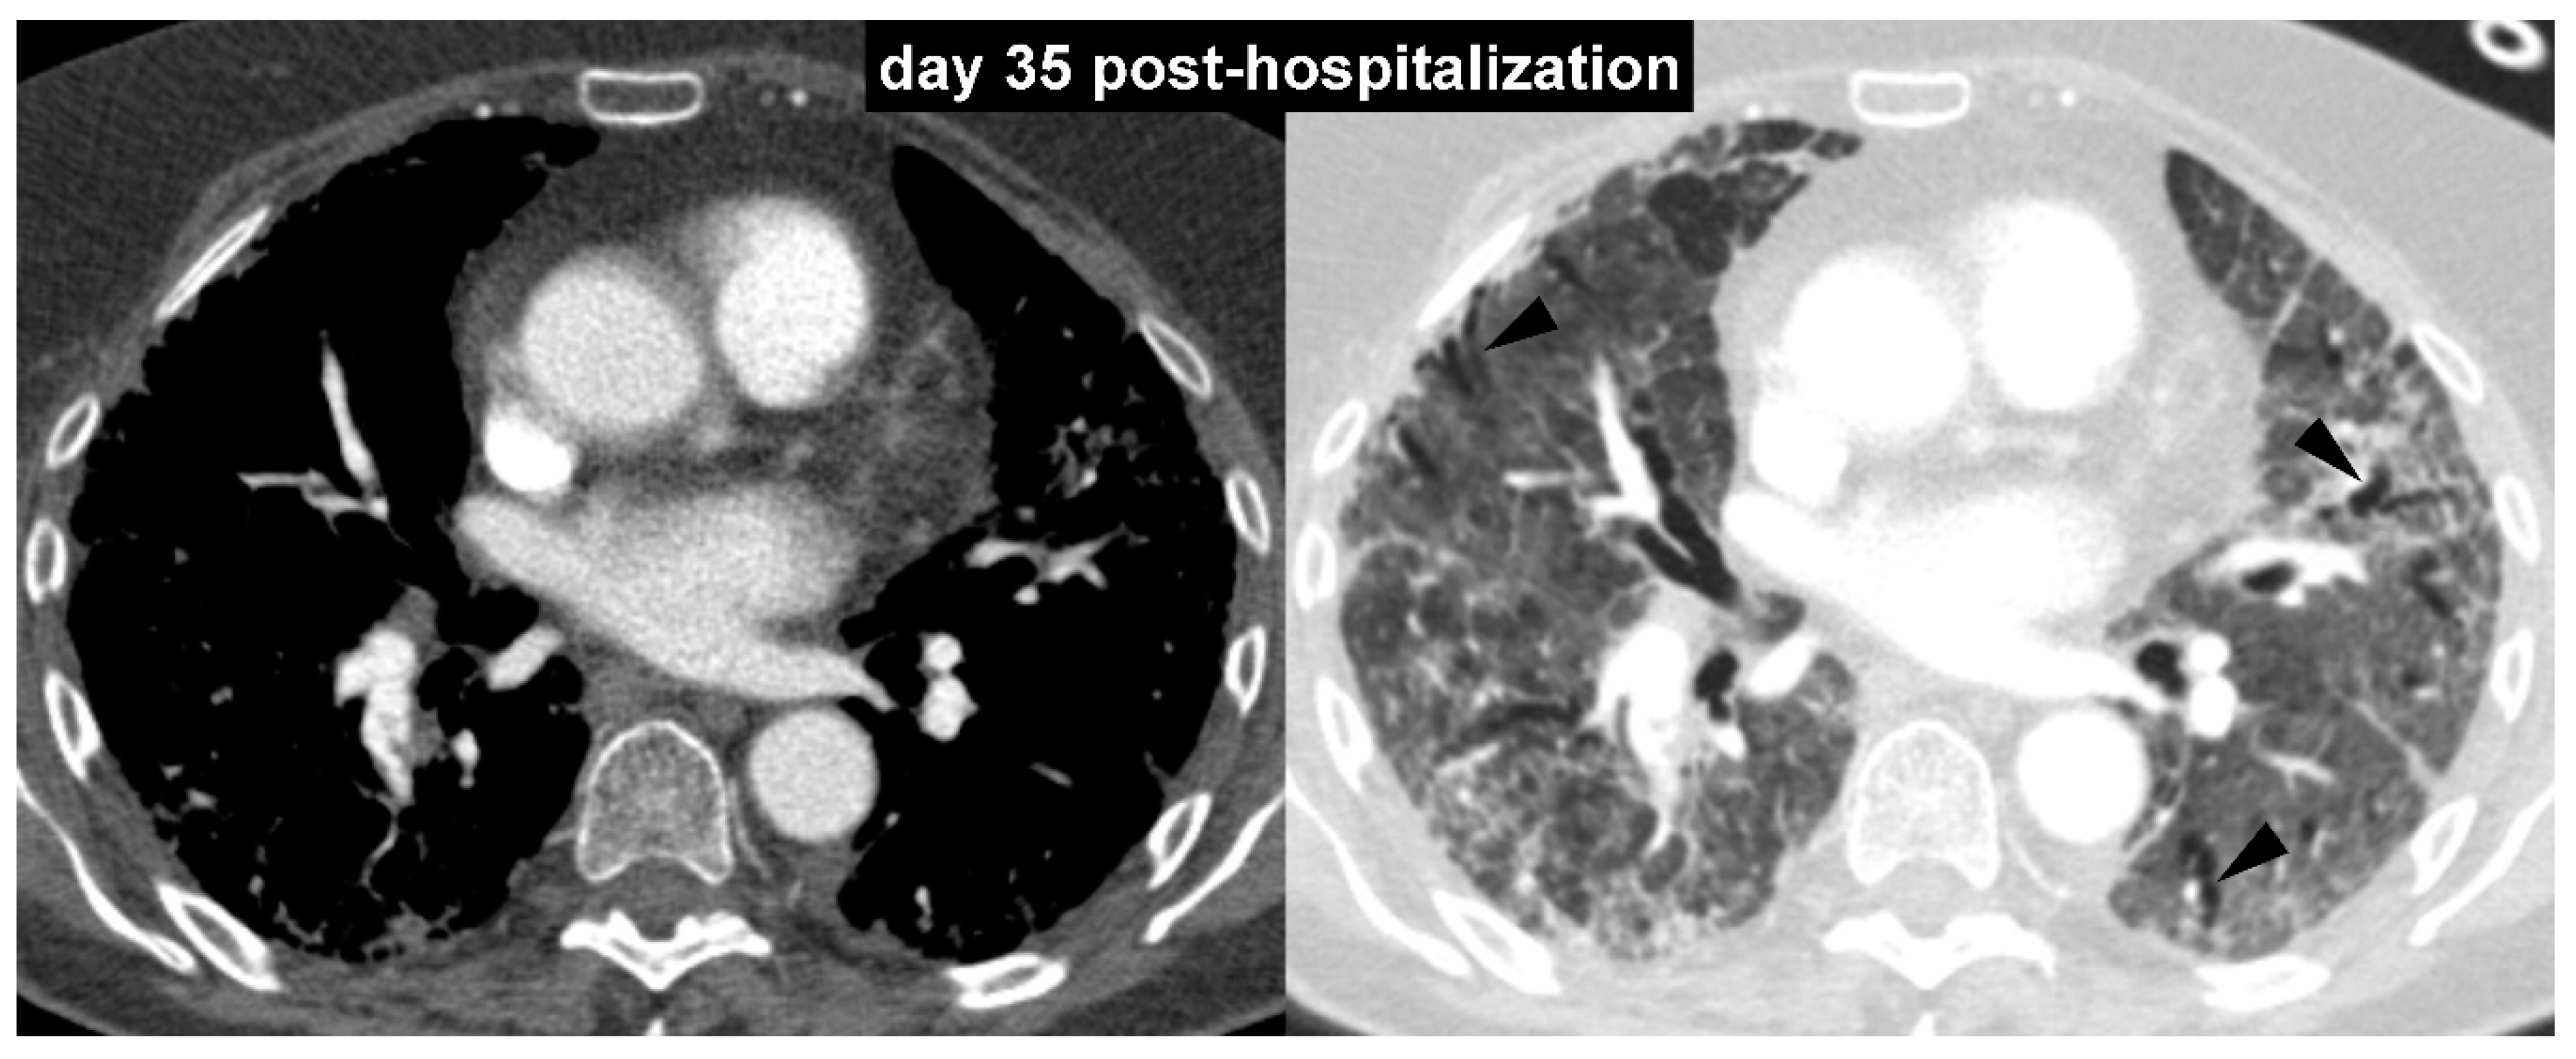

COVID-19 Pneumonia: Three Thoracic Complications in the Same Patient

Borghesi, A.; Aggiusti, C.; Farina, D.; Maroldi, R.; Muiesan, M.L. COVID-19 Pneumonia: Three Thoracic Complications in the Same Patient. Diagnostics 2020, 10, 498. https://doi.org/10.3390/diagnostics10070498